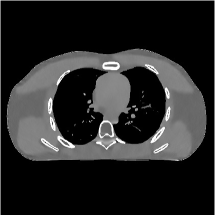

III.C. Low-dose Experiments with Mayo Clinic Data

First, we study transform training based on Mayo Clinic data. As shown in Fig. 6, seven slices obtained at regular dose from three patients are used for transform learning. The number of pixels . Similar to the phantom experiments, overlapping patches are extracted with a patch stride. The number of overall training patches is about . We set for ST, , , for MARS2, , , , , for MARS3, , , , , , , , , for MARS5, , , , , , , , , , , , , for MARS7. The iteration number in Algorithm 1. Fig. 7 illustrates the learned transforms obtained with Mayo Clinic data. Different from the XCAT phantom case, these transforms up to MARS5 display more complex features and structures. The rich features of the MARS models better sparsify the training images over layers compared to the single-layer model (ST).